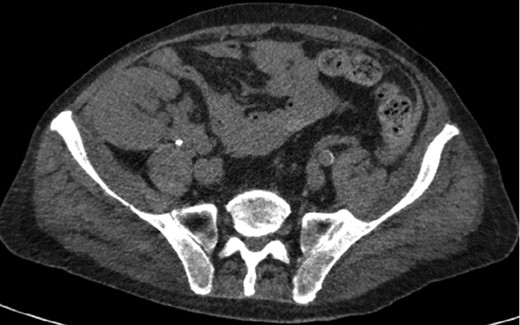

A 68-year-old male with history of living donor renal transplant presented to the ED with acute onset of profound weakness, fatigue, left upper quadrant abdominal pain, hypotension and lactic acidosis. On exam, he exhibited mild left upper quadrant and epigastric tenderness without evidence of peritonitis. CT imaging demonstrated splenomegaly with a large splenic hematoma measuring 15.7 × 9.2 × 12 cm and associated hemoperitoneum (Figs 1–3). In addition, innumerable osseous lytic lesions were identified. Given these findings, emergent surgical consultation was obtained and his coagulopathy reversed. He remained hypotensive despite resuscitation, thus was taken for laparotomy. Upon abdominal entry, a large amount of old clot was evacuated. The abdomen was packed in all quadrants in the standard fashion. Upon removal of the left upper quadrant packs, active hemorrhage began to well from the region of the spleen which was mobilized and removed via splenectomy. Upon gross inspection, the spleen was hyperemic and abnormally indurated, with an avulsion type injury extending several centimeters across the inferior pole. There was no evidence of pseudoaneurysm or other gross pathology. Given the patient was mildly hypothermic and coagulopathic with continued oozing from the retroperitoneum, the decision was made to pack the splenic fossa and place a temporary wound vac. The patient was transported to the ICU for resuscitation and brought back to the OR the next morning for re-exploration and closure. Despite hemodynamic stabilization, he underwent a prolonged hospitalization complicated by atrial fibrillation, renal allograft failure, VAP, and ultimately PEA arrest progressing to asystole. He died 6 weeks following splenectomy. The pathology from the spleen revealed splenomegaly with parenchyma that was replaced with amorphous and acellular eosinophilic material. Histologic staining (Thioflavin-T) was positive for amyloidosis, AL-type. Oncology was consulted based on these findings with concern for lymphoproliferative disorder given osseous findings on CT, splenic pathology, and history of immunosuppression. Bone marrow biopsy was subsequently obtained which showed more than 50% atypical plasma cells/plasma blasts (CD138+; PAX5 negative; EBV (EBER) negative) and no amyloidosis, consistent with multiple myeloma. Urine showed Bence-Jones protein. Serum immunofixation studies were remarkable for a monoclonal IgG lambda gammopathy, consistent with the diagnosis of AL amyloidosis associated with systemic myeloma.

Axial CT imaging showing hemoperitoneum secondary to splenic rupture.